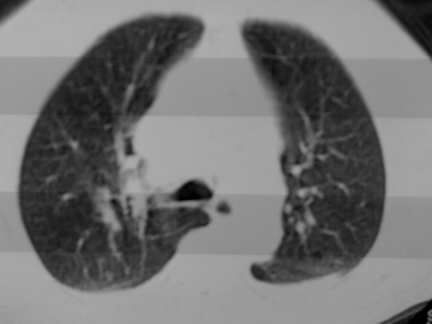

标题: CT13142:女 80 胸闷、气短、1w [打印本页]

标题: CT13142:女 80 胸闷、气短、1w

右肺炎性变,双侧甲状腺肿,胸膜肥厚。

右肺炎性变

气管,支气管软骨钙化。